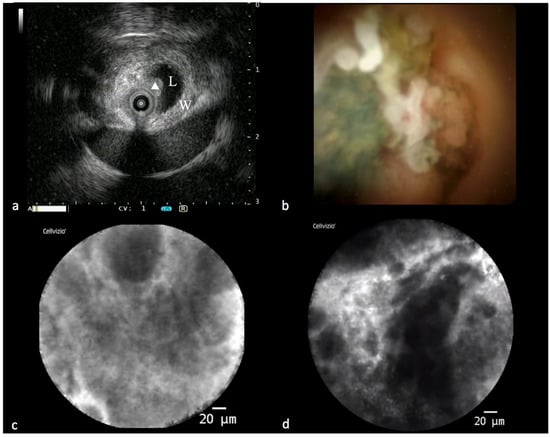

Figure 2.

Findings in a malignant biliary stricture during the “all in one technique”. (a) IDUS showing eccentric thickening of the bile duct wall with a polypoid profile (L: lumen; W: bile duct wall; triangle: polypoid-shaped thickening). (b) Cholangioscopic vision of a polypoid lesion of a common bile duct. (c,d) PCLE showing some features of malignancy according to the Miami classification for biliary stenosis (thick dark and white bands and dark clumps).

IBS can also benefit from this integrated approach. Nowadays, it is possible to offer the patient the so-called “all in one technique”, an integrated endoscopic approach that consists of performing, during the same ERCP session, IDUS, cholangioscopy, pCLE, intraductal tissue acquisition with dedicated forceps, brushing and drainage of the bile duct (Figure 2). This modality maximizes the diagnostic yield, accelerates the diagnosis and reduces the need to repeat one or more ERCPs with related risks [].